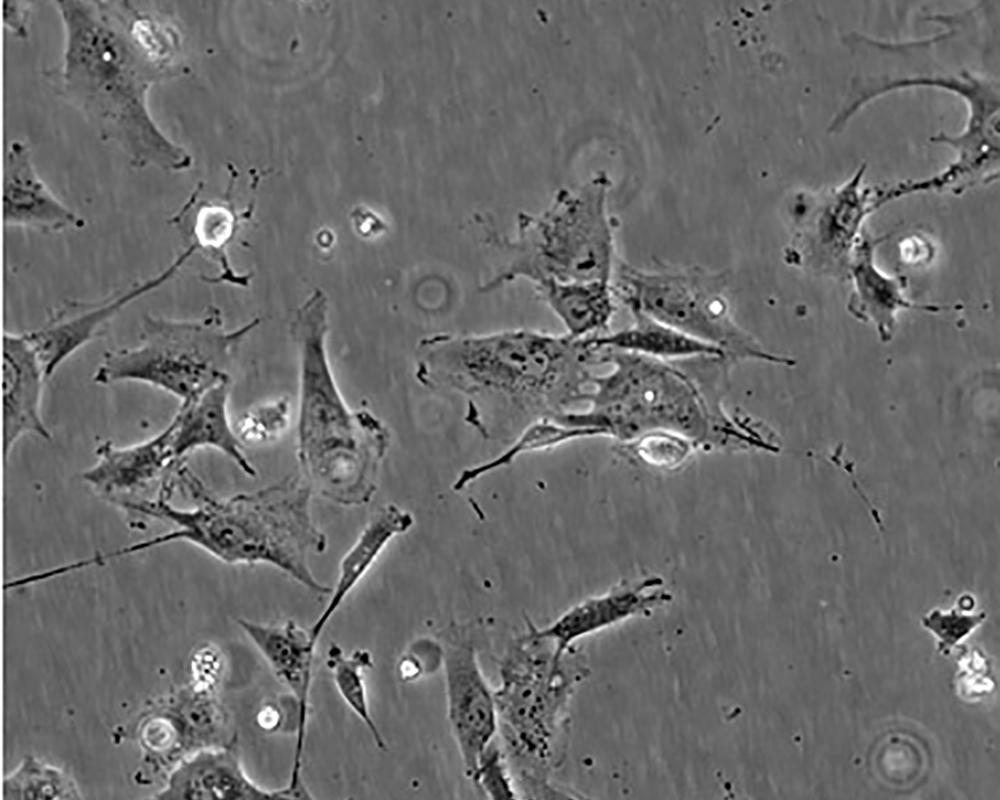

Hs 578T

產品名稱 Hs 578T

中文名稱 人乳腺癌細胞

組織來源 浸潤性導管癌;女性

形態特征 epithelial

細胞描述 The Hs 578T line had a mixed polygonal morphology initially, but a stellate cell type was selected for during passage and by cloning. Aggregates of casein protein granules, desmosomes, tight junctions, lipid droplets and vesicularized smooth endoplasmic reticulum were observed by electron microscopy. As with Hs 578Bst, no estrogen receptors or endogenous viruses were detected.